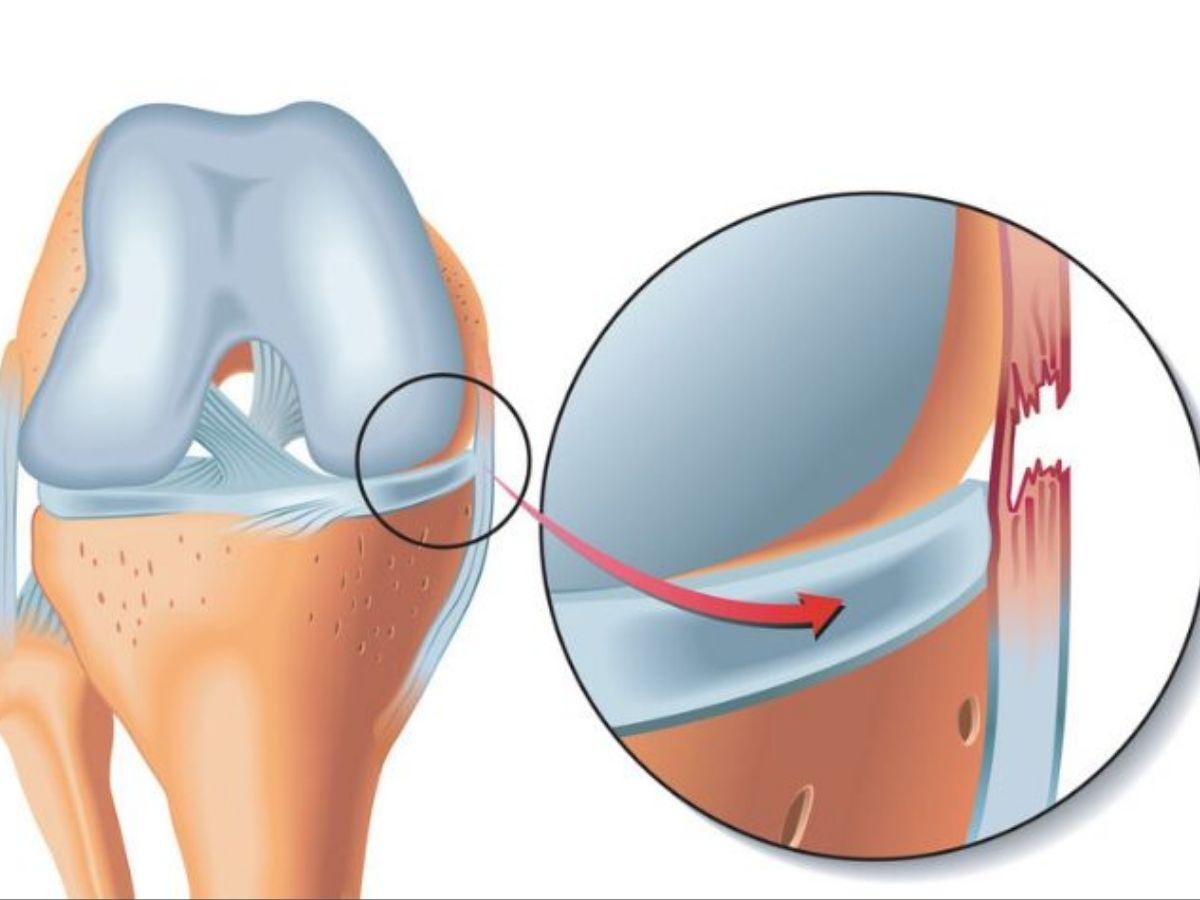

Rách sụn chêm (Meniscus tear)

Sụn chêm là bộ phận có tác dụng hấp thu lực tác động và ổn định hoạt động khớp gối. Nếu phần đầu gối bị xoắn hoặc tác động lực quá mạnh như chấn thương đầu gối khi ngã xe, chấn thương chân khi đá bóng có thể gây rách sụn chêm, gây cảm giác đau nhói khi xoay hoặc cử động khác, khó di chuyển và sưng đau trong thời gian dài.

Rách sụn chêm (Nguồn: Bệnh viện Thống Nhất)